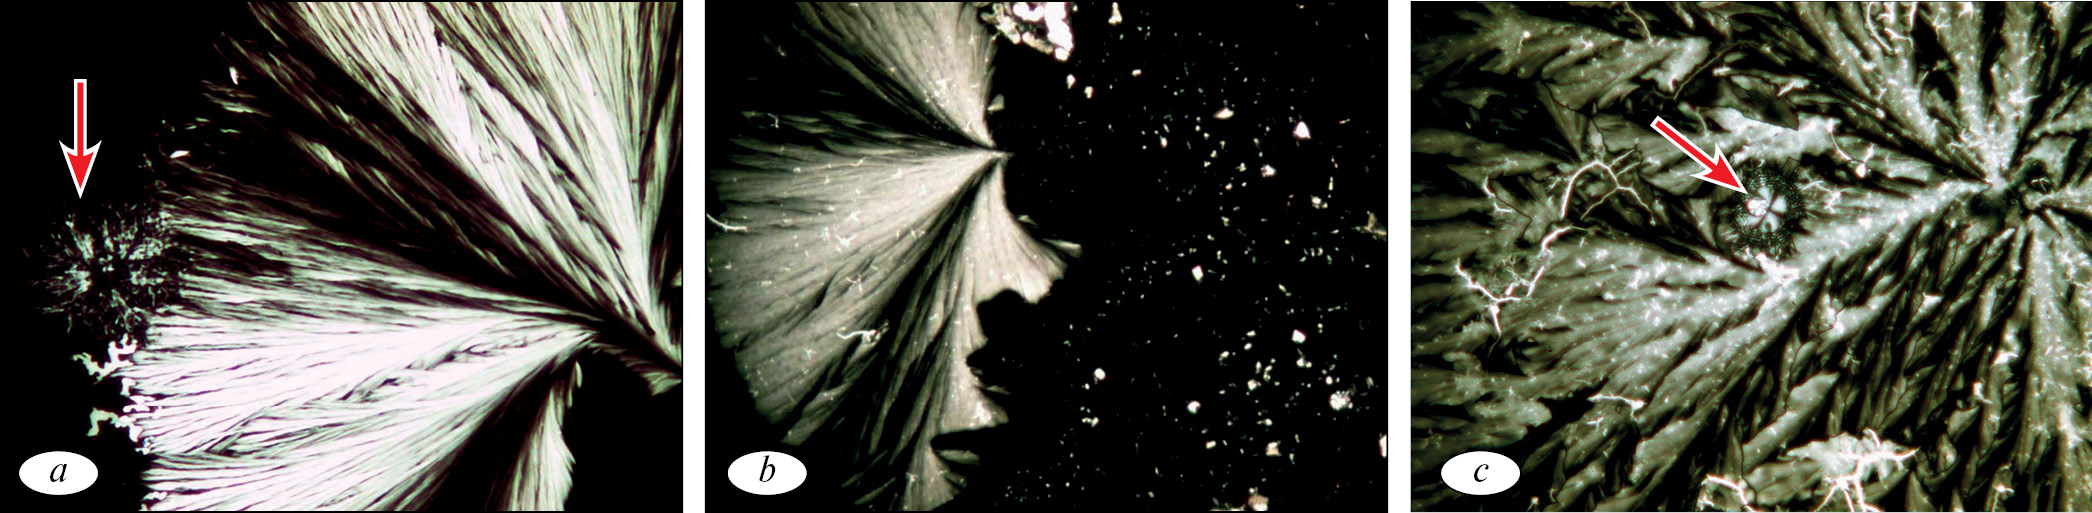

Исследование анизоморфонов трех проб сыворотки крови методом краевой дегидратации (аналитические ячейки) показало четкие различия в их структуре. В контрольной пробе (проба 1) изотропные зернистые микросферолиты находились в тесном контакте с макросферолитами, что свидетельствовало о напряжении иммунной реактивности организма (рис. 2, а).

Рис. 2. Анизоморфоны сыворотки крови пациентки К. в пробах: а (проба 1) — слияние изотропного зернистого микросферолита с макросферолитом (стрелка); b (проба 2) — россыпи мелких гранул (несформированные микросферолиты), часть из которых связана с макросферолитом без повреждения его структуры; c (проба 3) — аномальная импрегнация микросферолитов и их фрагментов в макросферолит (стрелка), выраженная деструкция макросферолита. Микроскопия в поляризованном свете. Увел. ×200

Fig. 2. Anisomorpha blood serum of the patient K. in the samples: a (sample 1) — merge isotropic granular microspherulites with microspherulites (arrow); b (sample 2) — the scattering of small granules (raw microporosity), some of which are associated with microspherulites without damaging its structure; in (sample 3) — an anomalous impregnation of microspheroidal and their fragments in microspherules (arrow), severe destruction of macroporosity. Microscopy in polarized light ×200

Анизоморфоны сыворотки крови пробы 2 (суточная инкубация со сплавом титана, алюминия и ванадия) представлены множественными россыпями мелких гранул, расположенных изолированно или связанных с макросферолитом. При этом структура макросферолита не имела повреждений (рис. 2, b). Подобная картина была описана нами ранее в сыворотке крови больных бронхиальной астмой в период обострения заболевания [5] и дает основание полагать, что контакт с этим сплавом вызывает активацию иммунологической реактивности организма пациента, сенсибилизированного к сплаву металлов. Это положение подтверждается выявлением в этой же пробе маркера усиленной пролиферации в виде каскада параллельных анизотропных линий (рис. 3, а).

Рис. 3. Анизоморфоны сыворотки крови: а (проба 2) — каскад параллельных анизотропных линий (маркер пролиферации), увел. ×100; b (проба 3) — волнистый микросферолит (маркер агрессии на ксеногенный фактор), увел. ×800. Микроскопия в поляризованном свете

Fig. 3. SC Anisomorphons: a (sample 2) — cascade of parallel anisotropic lines (proliferation marker), ×100; b (sample 3) — wavy microspherolite (marker of aggression on xenogenic factor), ×800. Microscopy in polarized light

Почти все макросферолиты сыворотки крови пробы 3 (сплав кобальта, хрома и молибдена) имели выраженную деструкцию в виде изъеденности их лучевых элементов, при этом они были импрегнированы микросферолитами и их фрагментами, а также включениями в виде линейных структур (рис. 2, с). В аналитических ячейках сыворотки крови пробы 3 выявлялось небольшое число волнистых микросферолитов (рис. 3, b), которые входили в аномальную агрегацию с деструктивными макросферолитами или оставались изолированными. Известно, что данный маркер свидетельствует об агрессивности протекающего процесса. Так, появление волнистого микросферолита в сыворотке крови онкологических больных в процессе лечения означает прогрессию злокачественного роста в результате трансформации злокачественных клеток в наиболее агрессивный клон [4].